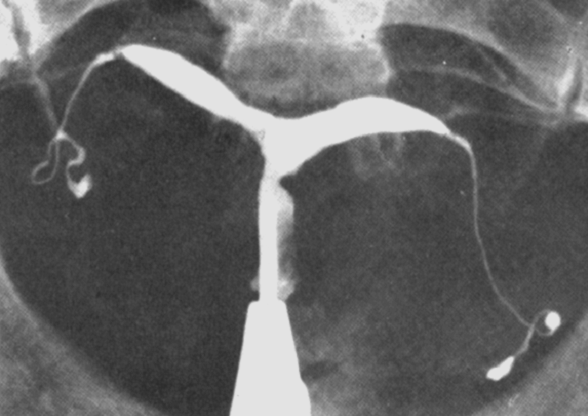

Медицинские снимки: Проходимость маточных труб

Раздел: Кадры-подсказки